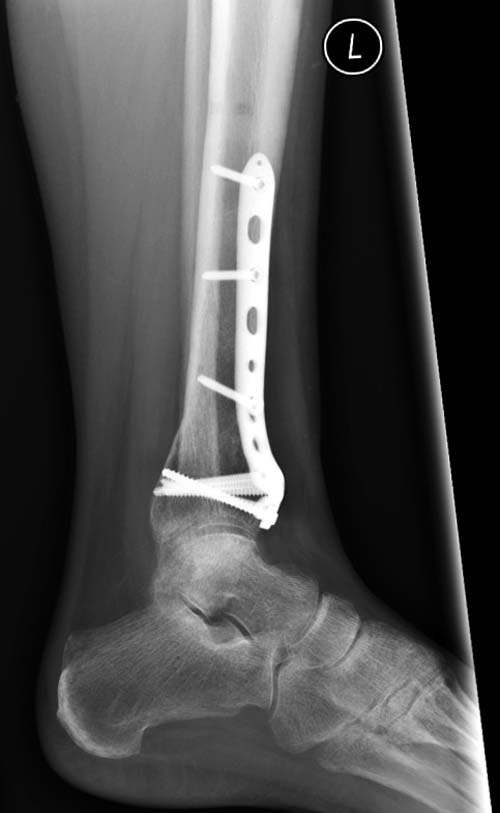

Второй случай в результате скоростной травмы, кроме пилона, вовлечение

других органов! Отек при поступлении и открытый перелом на другой

стороне. В таких случаях нет смысла спешить, и временный наружный

фиксатор на несколько дней. После спадения отека фиксация

передне-наружной пластиной.  Реабилитация - ранние движения, без

нагрузки.